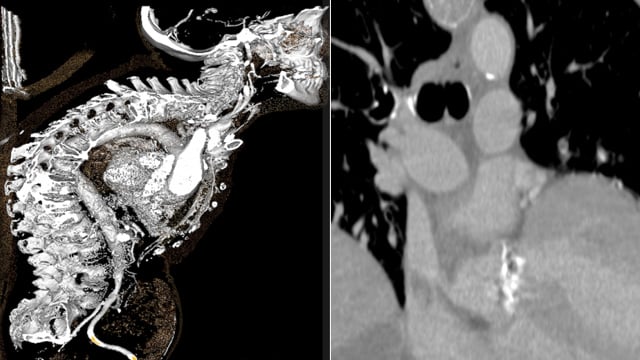

TAVI: complex vascular access

17 Nov 2025 – From PCR London Valves 2025

This session addresses the challenges of complex vascular access in transcatheter aortic valve implantation (TAVI). It discusses strategies for navigating difficult thoraco-abdominal aortic anatomies, managing double aortic arches, and overcoming hostile femoral access. Case studies illustrate meticulous planning and innovative solutions essential for successful TAVI in...

TAVI: challenging anatomies

17 Nov 2025 – From PCR London Valves 2025

This session explores the management of challenging anatomical conditions in TAVI procedures. Topics include strategies for difficult self-expandable valve delivery angles, addressing complications occurring during and after TAVI, and approaches for patients with severe kyphosis or complex structural abnormalities such as aneurysms and septal anomalies.